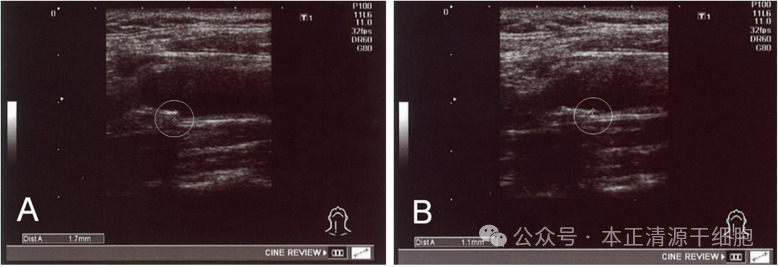

研究特别追踪了一名56岁男性患者,该患者在接受间充质干细胞治疗前3个月和治疗后6个月分别进行了颈总动脉内膜中层厚度(IMT)的检测。其颈动脉IMT在干细胞治疗四个月后显著改善——从1.7mm降至1.1mm。研究者认为,这可能得益于干细胞抑制炎症和促进血管修复的双重作用。